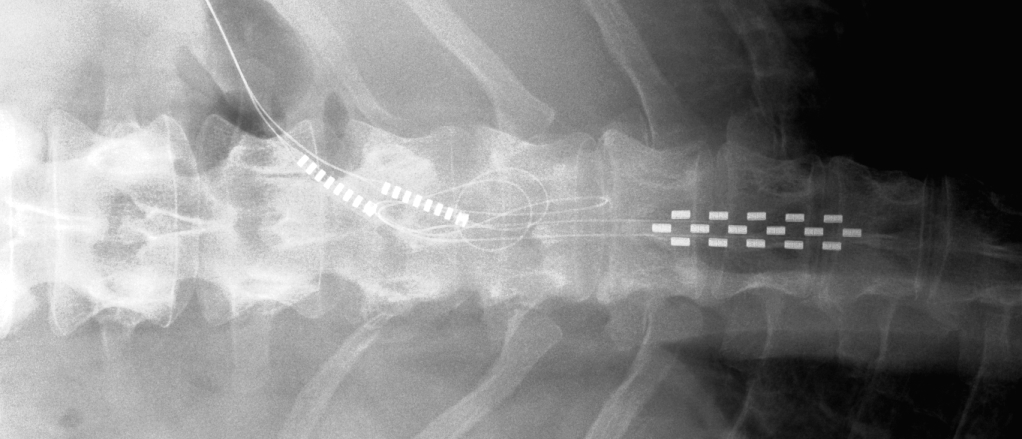

A spinal cord stimulator is an implanted device under battery power. Doctors use these ‘pain pacemakers’ as they call them to treat certain pain conditions. Basically, they use them to send electrical signals to select areas of the spinal cord. The commonest use is relieving suffering among patients with failed back surgery syndrome.

Swiss doctors have found a brilliant new application for a spinal cord stimulator. They recruited a man whom doctors thought would never walk again, because of a severed spinal cord. Then they inserted the device around his spine and used it to amplify signals from his brain to his legs.

A spinal cord stimulator uses a tiny battery that may last for several years depending on individual use. When it fails, a surgeon has to replace it. However there has been good progress with commercial rechargers placed on the patient’s skin over the device and sending a signal to its antenna.